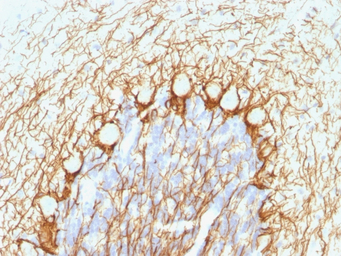

IHC-P analysis of rat cerebellum tissue using GTX57165 NF-H (phospho) antibody [NE14].

IHC-P analysis of human cerebellum tissue using GTX57165 NF-H (phospho) antibody [NE14].